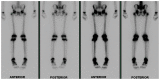

Less than 10% of chondrosarcomas occur in children. In addition, as little as 0.5% of low-grade chondrosarcomas arise secondarily from benign chondroid lesions. The presence of focal pain is often used to crudely distinguish a chondrosarcoma (which is usually managed with wide surgical excision), from a benign chondroid lesion (which can be followed by clinical exams and imaging surveillance). Given the difficulty of localizing pain in the pediatric population, initial radiology findings and short-interval follow-up, both imaging and clinical, are critical to accurately differentiate a chondrosarcoma from a benign chondroid lesion. To our knowledge, no case in the literature discusses a chondrosarcoma possibly arising secondarily from an enchondroma in a pediatric patient. We present a clinicopathologic and radiology review of conventional chondrosarcomas. We also attempt to further the understanding of how to manage a chondroid lesion in the pediatric patient with only vague or bilateral complaints of pain.